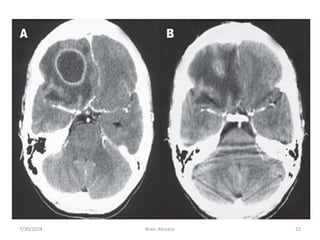

4. radiological characteristic of brain abscess

1. Brain CTS with contrast

• ring enhancement

• Multi loculation

• Multiplicity

• Finding of gas

7/30/2024 Brain Abscess 17